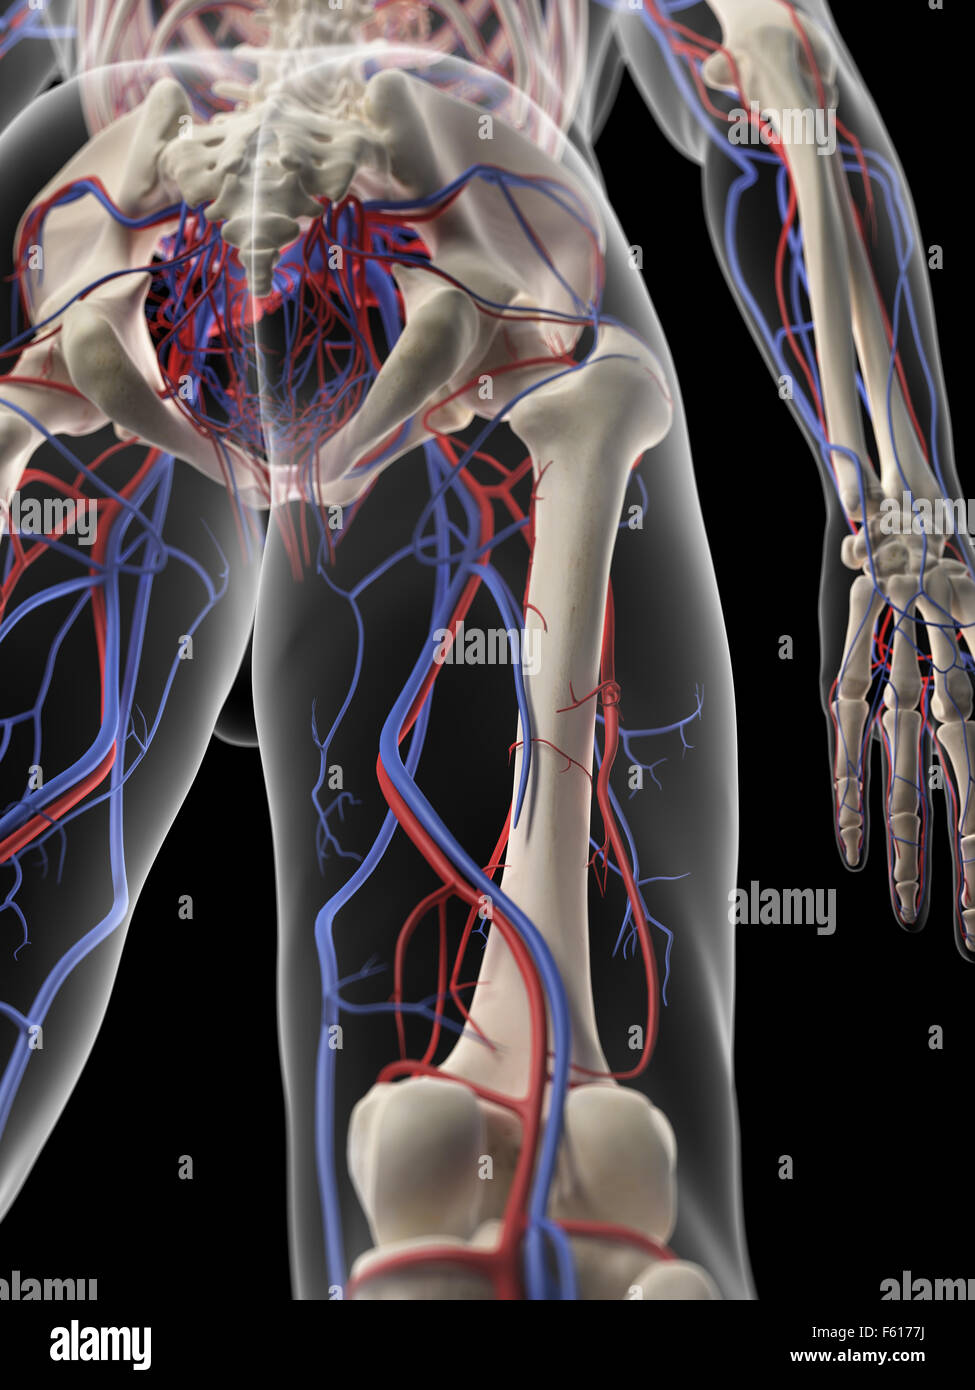

RF2BTEMBH–Schematische Darstellung des menschlichen Kreislaufsystems, der Herzanatomie und der Gehirnblutversorgung